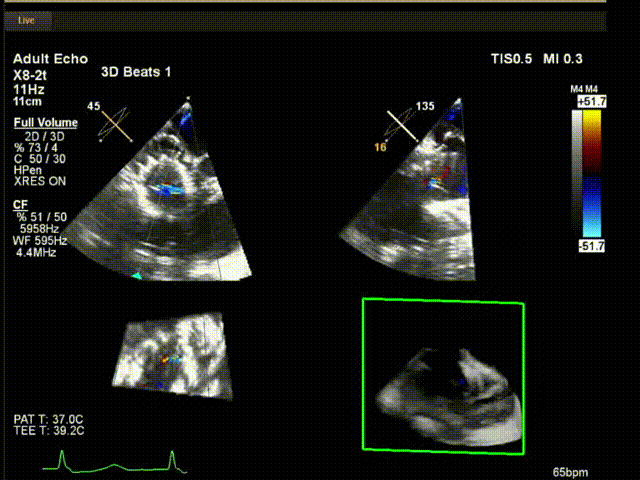

陸方林教授通過遠(yuǎn)程線上帶教的方式,與林逸賢教授團(tuán)隊(duì)共同完成了此次LuX-Valve Plus人工瓣膜的首例植入。術(shù)后食道超聲提示三尖瓣反流完全消失,無(wú)瓣周漏,且LuX-Valve Plus人工瓣膜的兩個(gè)夾持鍵成功抓取瓣葉,錨定牢固,人工瓣膜穩(wěn)定性良好。